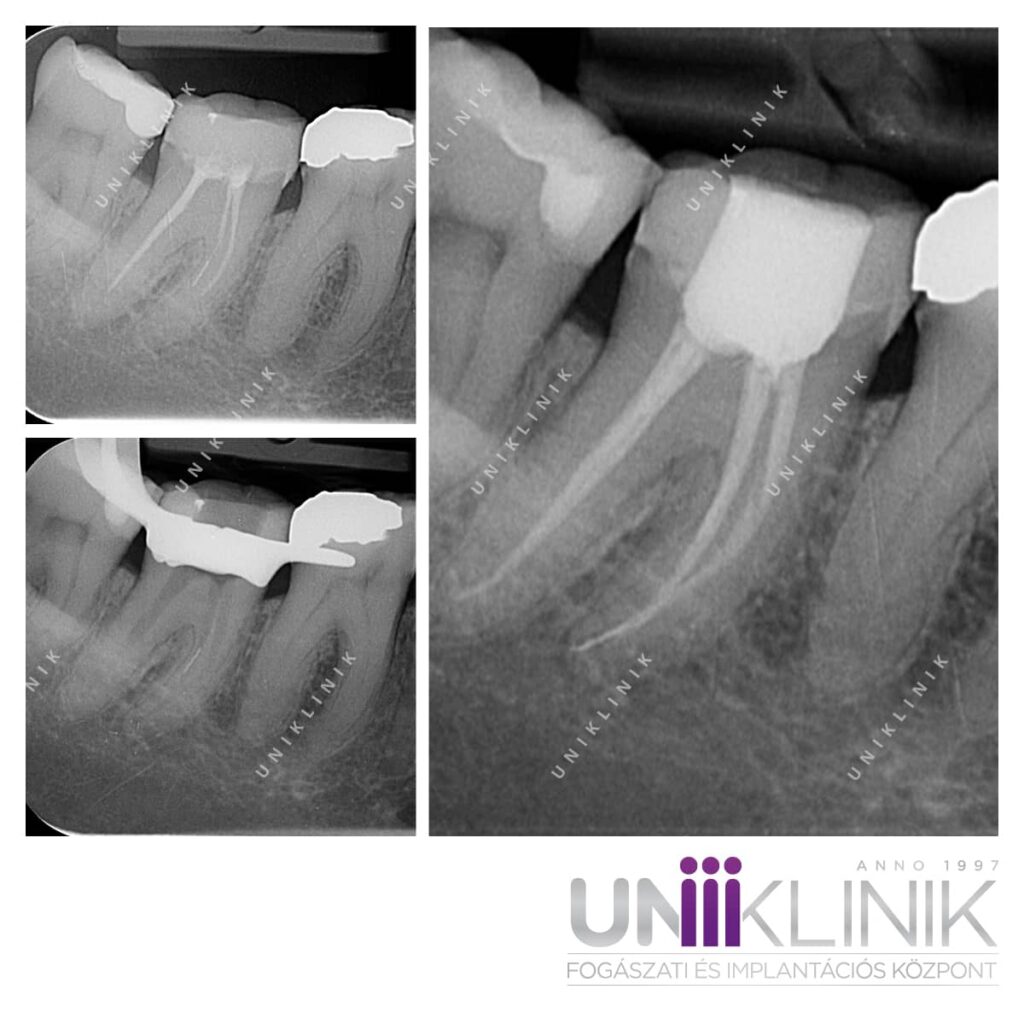

Szakterületem: mikroszkópos gyökérkezelés, gyökértöméscsere mikroszkóppal

A mikroszkópos gyökérkezelésben szereztem nagy jártasságot. Ezt a berendezést nem könnyű kezelni, ezért kevés a megfelelő tapasztalattal rendelkező szakember. Pedig a mikroszkóp segítségével a legparányibb gyökércsatornák is felderíthetők és kezelhetők. Ha sikeresen kezelünk egy problémás fogat, az azt jelenti, hogy megmentettük a páciens számára: nem kell kihúzni, és szerencsés esetben élete végéig megmarad. A saját fog pedig nagy érték!

Dr. Molnár Katalin Esettanulmányai